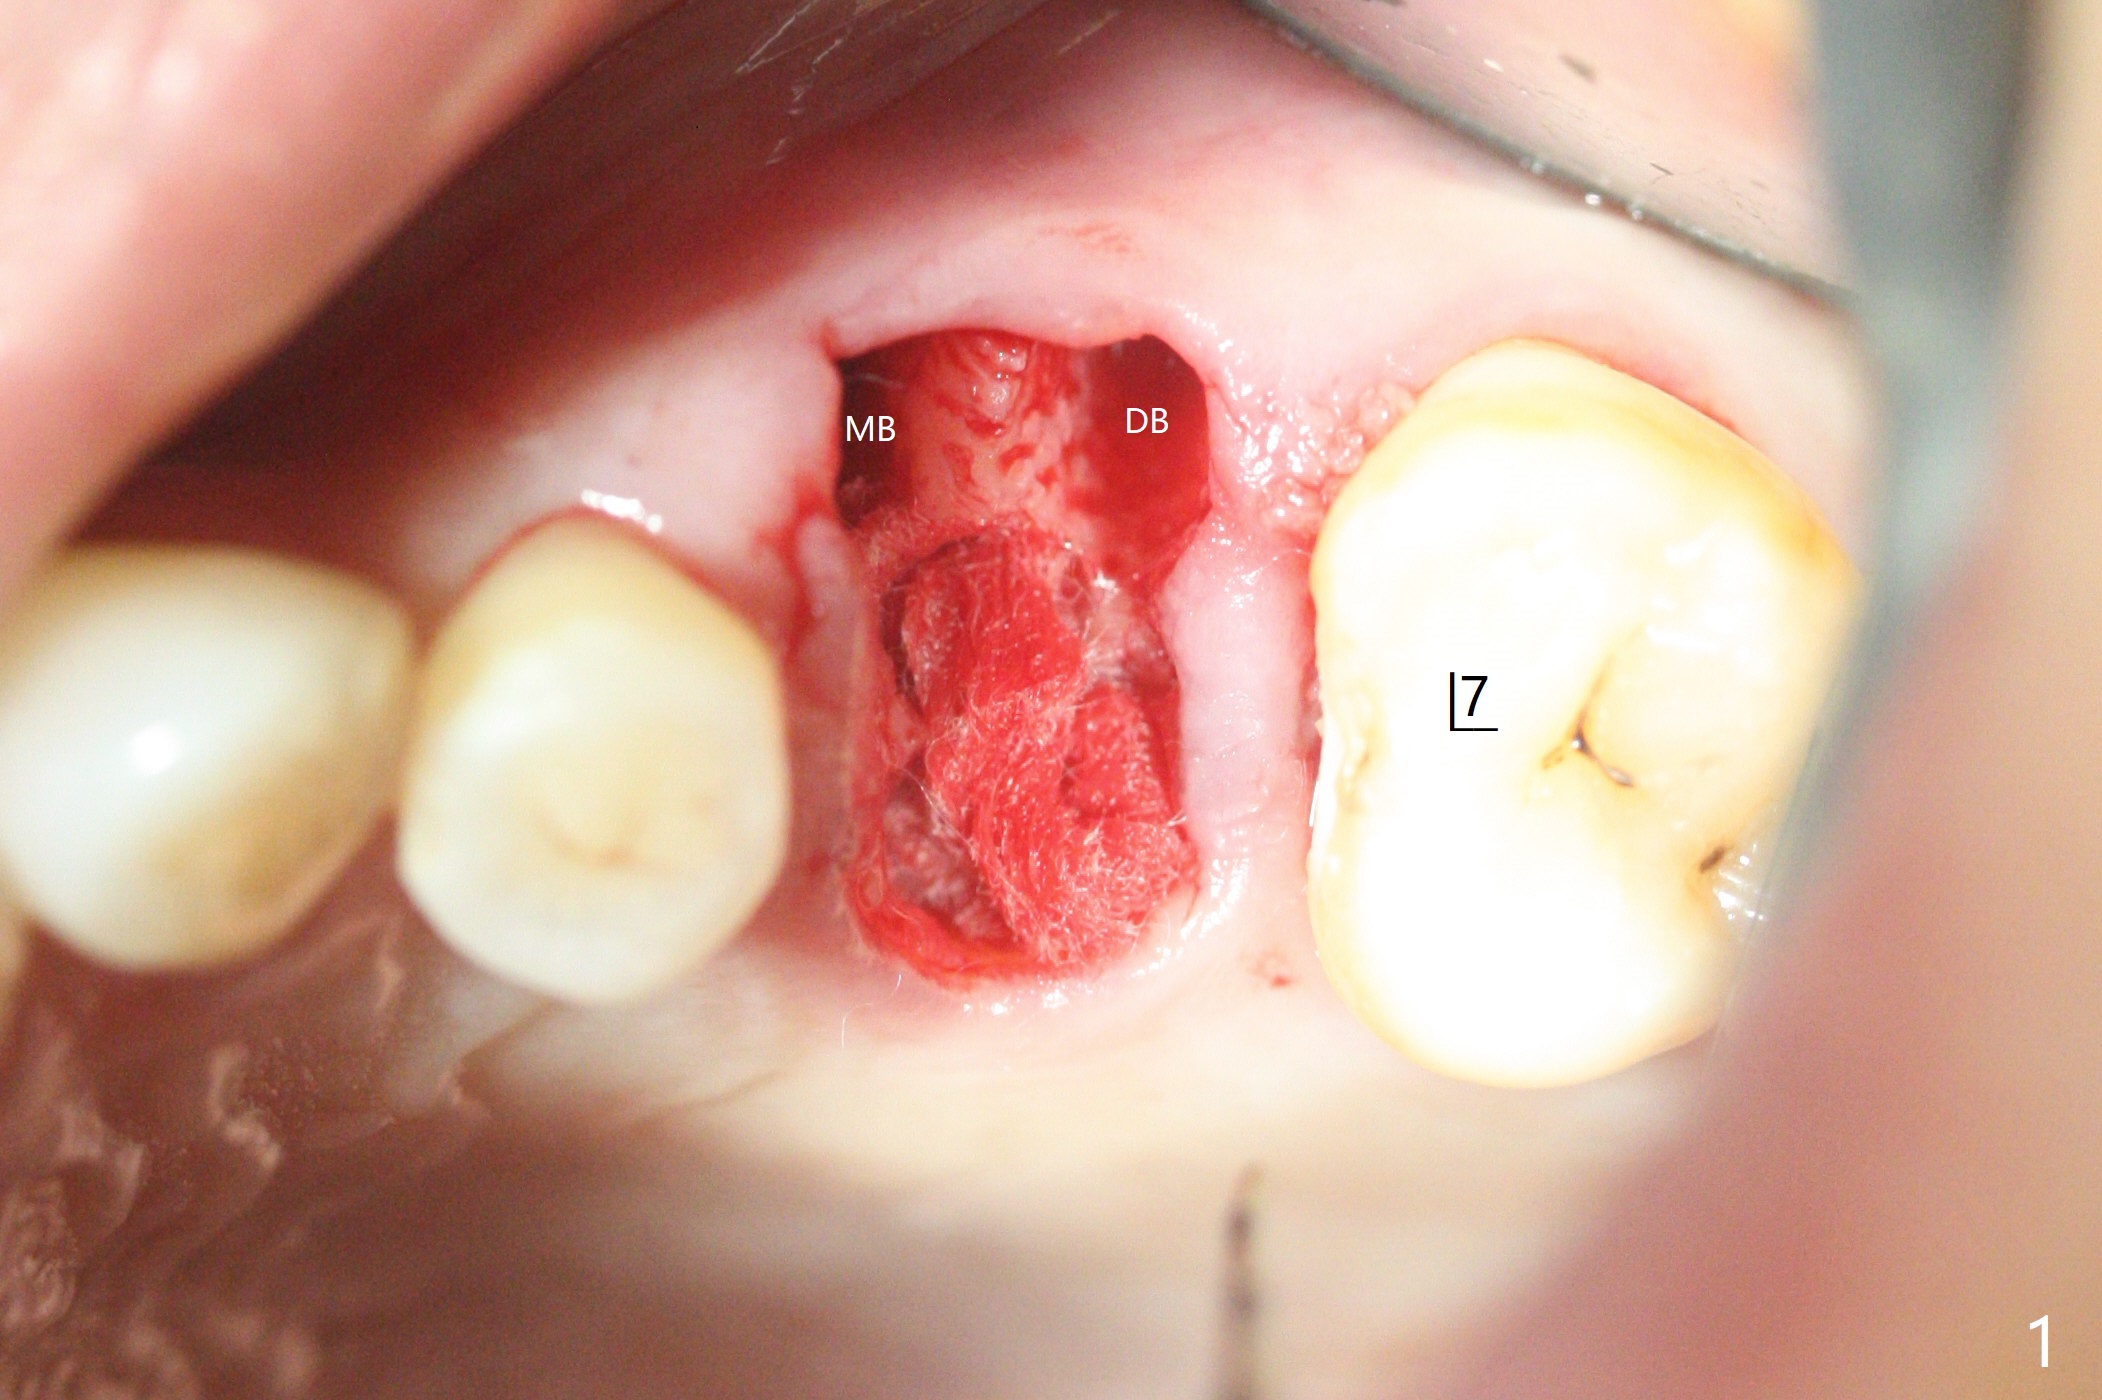

虽然没有保留左上6牙根,但是导板好像帮助钻洞(O)正好位于中隔当中(图一,二)。使用4.5(不是4.0)x10毫米钻头后,粘性骨粉和报废植体完成上颌窦提升术(图三:S)。拔除第一磨牙后发现第二磨牙近中面龋齿,立刻进行保守修补(图三:箭头);两个磨牙之间还有骨质吸收(*)。放置正式植体(10Ncm)后(图四),三个牙槽窝填入骨粉,包括近中颊侧(MB)和远中颊侧(DB),这时磨牙间缺损初步填补(*),然后放置基台以及基台周围骨粉,进一步充填磨牙间缺失(图五:*)。术后临时牙冠脱落两次,病人自己放回去,术后一周取出牙冠,骨粉还在(图六),腭侧有单纯疱疹病变(图七:>),开抗病毒漱口水处方,然后使用临时粘固粉。术后7个月15号牙近中牙槽嵴增高大约1.4毫米(图八:空箭头,从近中最颈部树脂算起)。术后七个月临时牙冠一直使用,防止食物坎塞,有利于骨质再生。术后7个月基台在口内没有更动(术中手拧紧),牙冠口内粘固,少量粘固剂遗留(图八:^)。牙冠/基台取出,去除粘固剂,牙冠/基台就位,用扳手拧紧(30 Ncm),基台与植体仍保持完全接触(图九)。只要植体植入角度好,没有倒凹,牙冠/基台再次就位就没有问题。